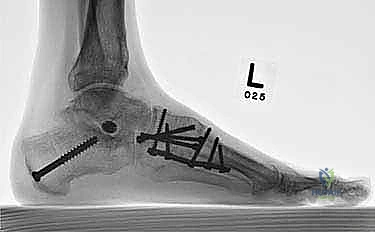

- الأشعة السينية أثناء الوقوف (Weight-bearing X-rays): وهي أهم أداة تشخيصية. الأشعة العادية والسرير فارغ لا تظهر المشكلة الحقيقية؛ يجب التقاط الأشعة والمريض يقف ليتحمل وزن الجسم، مما يظهر الانهيار الفعلي للمفاصل وتضيق المسافات بين العظام.

لضمان التحام العظام لتصبح عظمة واحدة صلبة، يجب تثبيتها بقوة هائلة حتى لا تتحرك أثناء فترة الشفاء. يتم استخدام مسامير معدنية متطورة (Screws)، أو شرائح معدنية خاصة (Plates)، أو دبابيس طبية متخصصة (Staples) مصنوعة من التيتانيوم الآمن على الجسم.

بعد التأكد التام من وضع العظام وثباتها باستخدام جهاز الأشعة السينية داخل غرفة العمليات (C-Arm)، يتم إغلاق الشقوق الج